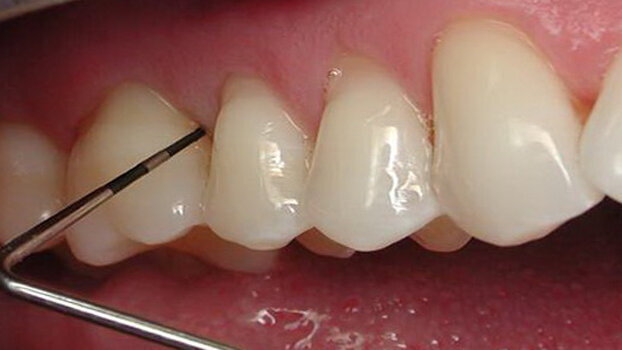

The diode laser makes restorative dentistry a breeze (Picasso, AMD LASERS). Any gingival tissue that covers a tooth during preparation can be easily removed as haemostasis is simultaneously achieved, as shown in Figs. 2-6. The restoration is no longer compromised due to poor gingival conditions. There is no more battling with unruly soft tissue and blood. Excess gingival tissue can be readily managed (Figs. 7-8) for improved restorative access to Class V preparation (ezlase, Biolase Technology)

Gingival troughing prior to taking impression, shown in Figs. 6-7 (Picasso, AMD LASERS) ensures an accurate impression (particularly at the all-important margins) and an improved restorative outcome. Packing cord is no longer necessary.